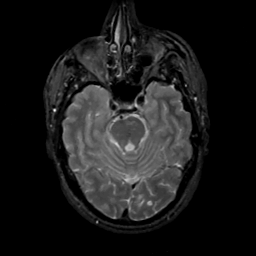

MR Study #14, June 2, 1991 -- Slice #16

[Home][Help][Clinical][Tour 1][Tour 2] Slice 16